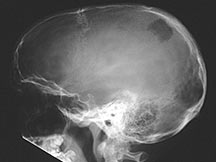

- Any bone but 90% have skull involvement

- Skull